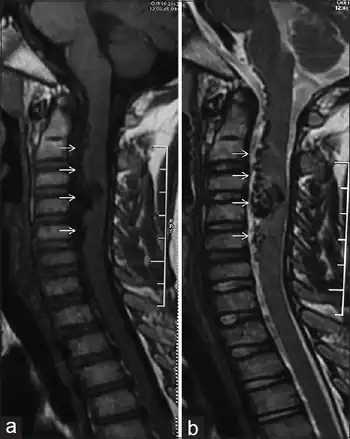

| a,b) Spinal arteriovenous malformation | |

Spinal arteriovenous malformations

Spinal arteriovenous malformations (AVMs, or angiomatous malformations) are congenital (from birth) abnormalities of blood vessels. Arteries that directly communicate with veins bypass the capillary network (which has not yet developed) and thus creates a shunt. AVMs appear as a mass of convoluted, dilated vessels. In regards to the spinal cord, they are usually located in the thoracolumbar region (between the thoracic and lumbar regions, 60% of the time), as opposed to the upper thoracic (20%) and cervical regions (approximately 15%). Cervical malformations arise from the anterior spinal artery and lie within the cord, whereas thoracolumbar malformations can be internal, external or encompass both areas of the cord.[3]

Malformations can be recognised as part of an acute illness or gradual onset disease. In diseases such as subarachnoid hemorrhage, signs and symptoms include headache, neck stiffness and back and leg pain. Extradural, subdural and intramedullary hematomas are all signs of acute cord compression. Gradual onset diseases are more common (85-90% of all diseases leading to a diagnosis of malformation) and are usually due to an increased venous pressure. Other factors such as thrombosis or arachnoiditis can be involved. A bruit (unusual blood sounds) may be heard overlying the spinal arteriovenous malformation. Very occasionally, nevus (moles) or angiolipomas are found.[3]

Myelography is used to confirm the diagnosis of AVMs and it shows 'snake-like' vessels on the cord's surface. If the myelogram is positive, angiography is required to show the extent of malformation and the exact site of the shunt. Magnetic resonance imaging (MRI) may show the appropriate area. If AVMs are left untreated, 50% of patients with gradual symptoms will be unable to walk within 3 years of onset. Surgical occlusion has been shown to halt the progression and may improve any gait or incontinence.[3][6]